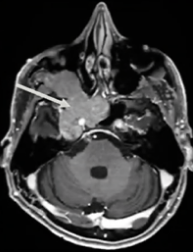

2012年,53岁的Leo突然发现自己嗅觉减退、视力下降时,就医检查发现右侧梅克尔腔脑膜瘤,随即进行了手术。谁能想到7年过后,脑膜瘤再次卷土重来,出现严重的V1(嗅神经)、V2(视神经)和V3(动眼神经)感觉减退和疼痛,症状比第一次手术前还要严重。磁共振成像(MRI)显示肿瘤大面积复发,延伸至海绵窦(CS)、后颅窝(PF)、蝶窦(SS)、翼腭窝(PPF)和颞下窝(ITF)。这个张牙舞爪的肿瘤,属实不太容易切除。

患者术前影像。(A)术前轴位T1加权钆增强磁共振成像(MRI),显示脑膜瘤延伸至后颅窝、海绵窦、眼眶和蝶窦。(B)肿瘤延伸至中颅窝、翼腭窝和颞下窝。(C)术前轴位计算机断层扫描(CT)显示蝶骨大翼侵蚀和蝶窦受累。